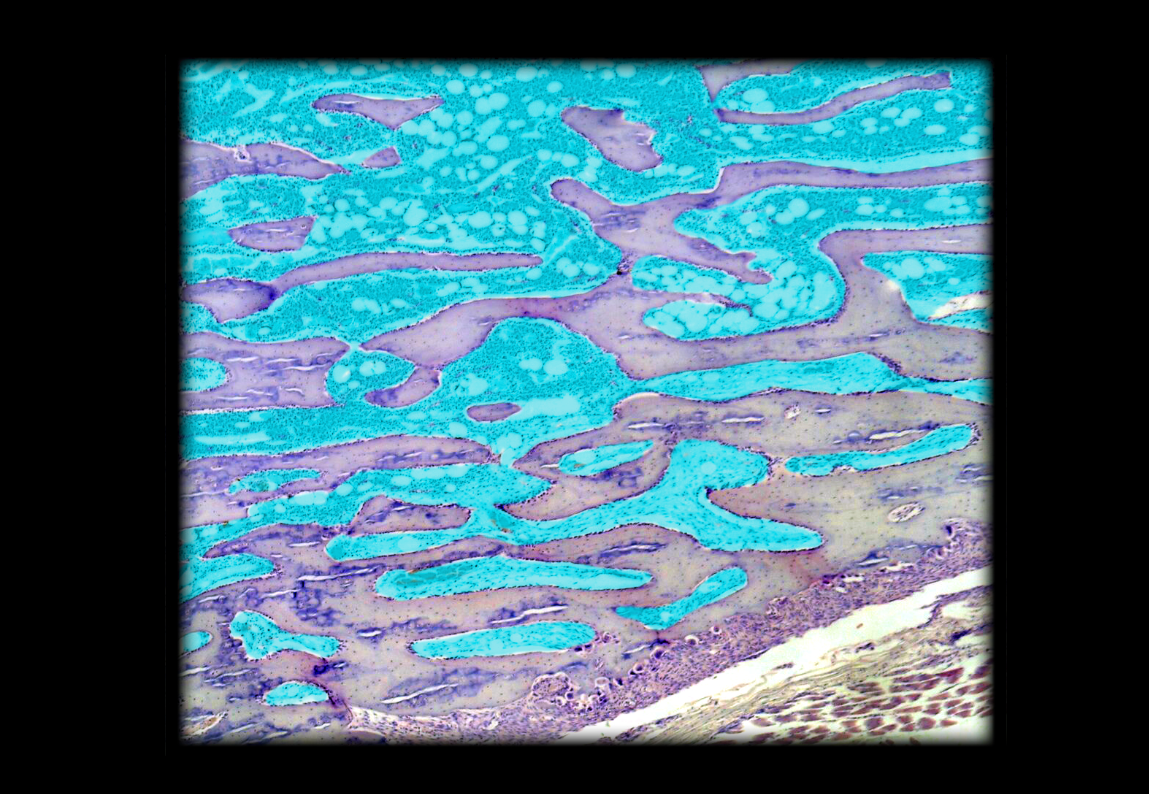

Marrow cavity in spongy bone

17

New cards

Trabecula of spongy bone